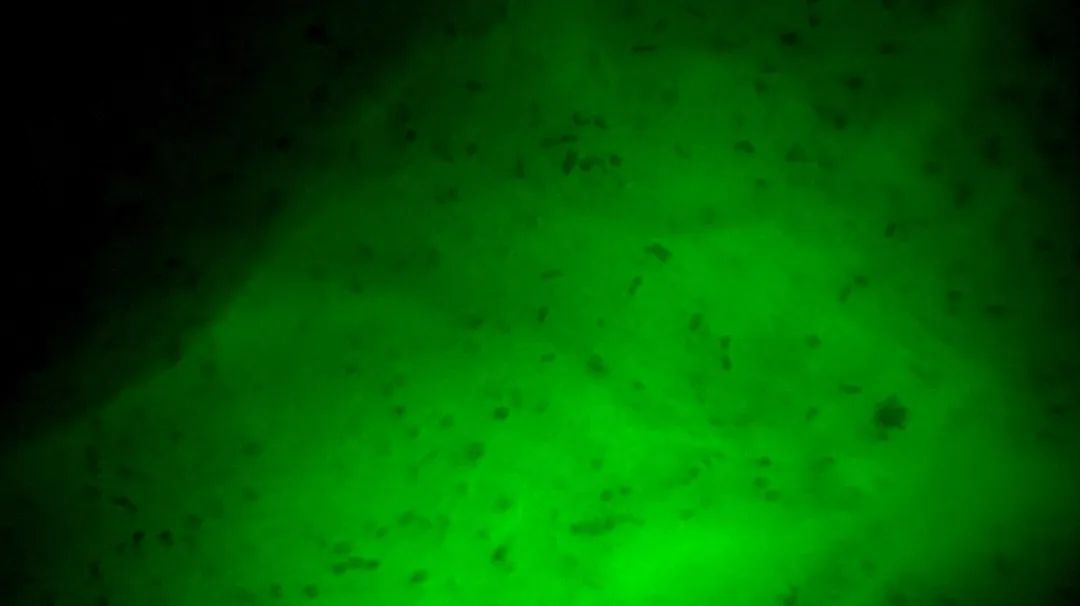

3次切緣掃查的EndoSCell?細(xì)胞圖像

1

陽(yáng)性,細(xì)胞核異型、密集、分布不均勻